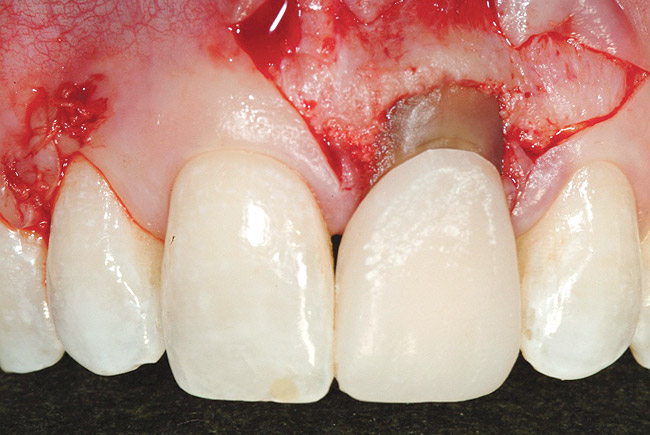

The patient opted for the third option. After administration of an appropriate local anesthetic, a frenectomy was performed using a Nd:Yag laser. This would allow for the loosening of the facial tissues and the coronal repositioning of the pouch at the termination of the procedure. After the frenectomy, the left central incisor was removed by an atraumatic technique preserving the soft tissue emergence profile (Figure 23). Debridement of the extraction socket preceded atraumatic site preparation techniques. A 3.5-mm diameter by 13-mm tapered implant (Prima Connect, Keystone Dental, www.keystonedental.com) was placed to the appropriate depth measurements planned.38,39

Figure 23  Case Three Atraumatic extraction, left central incisor.

Figure 23